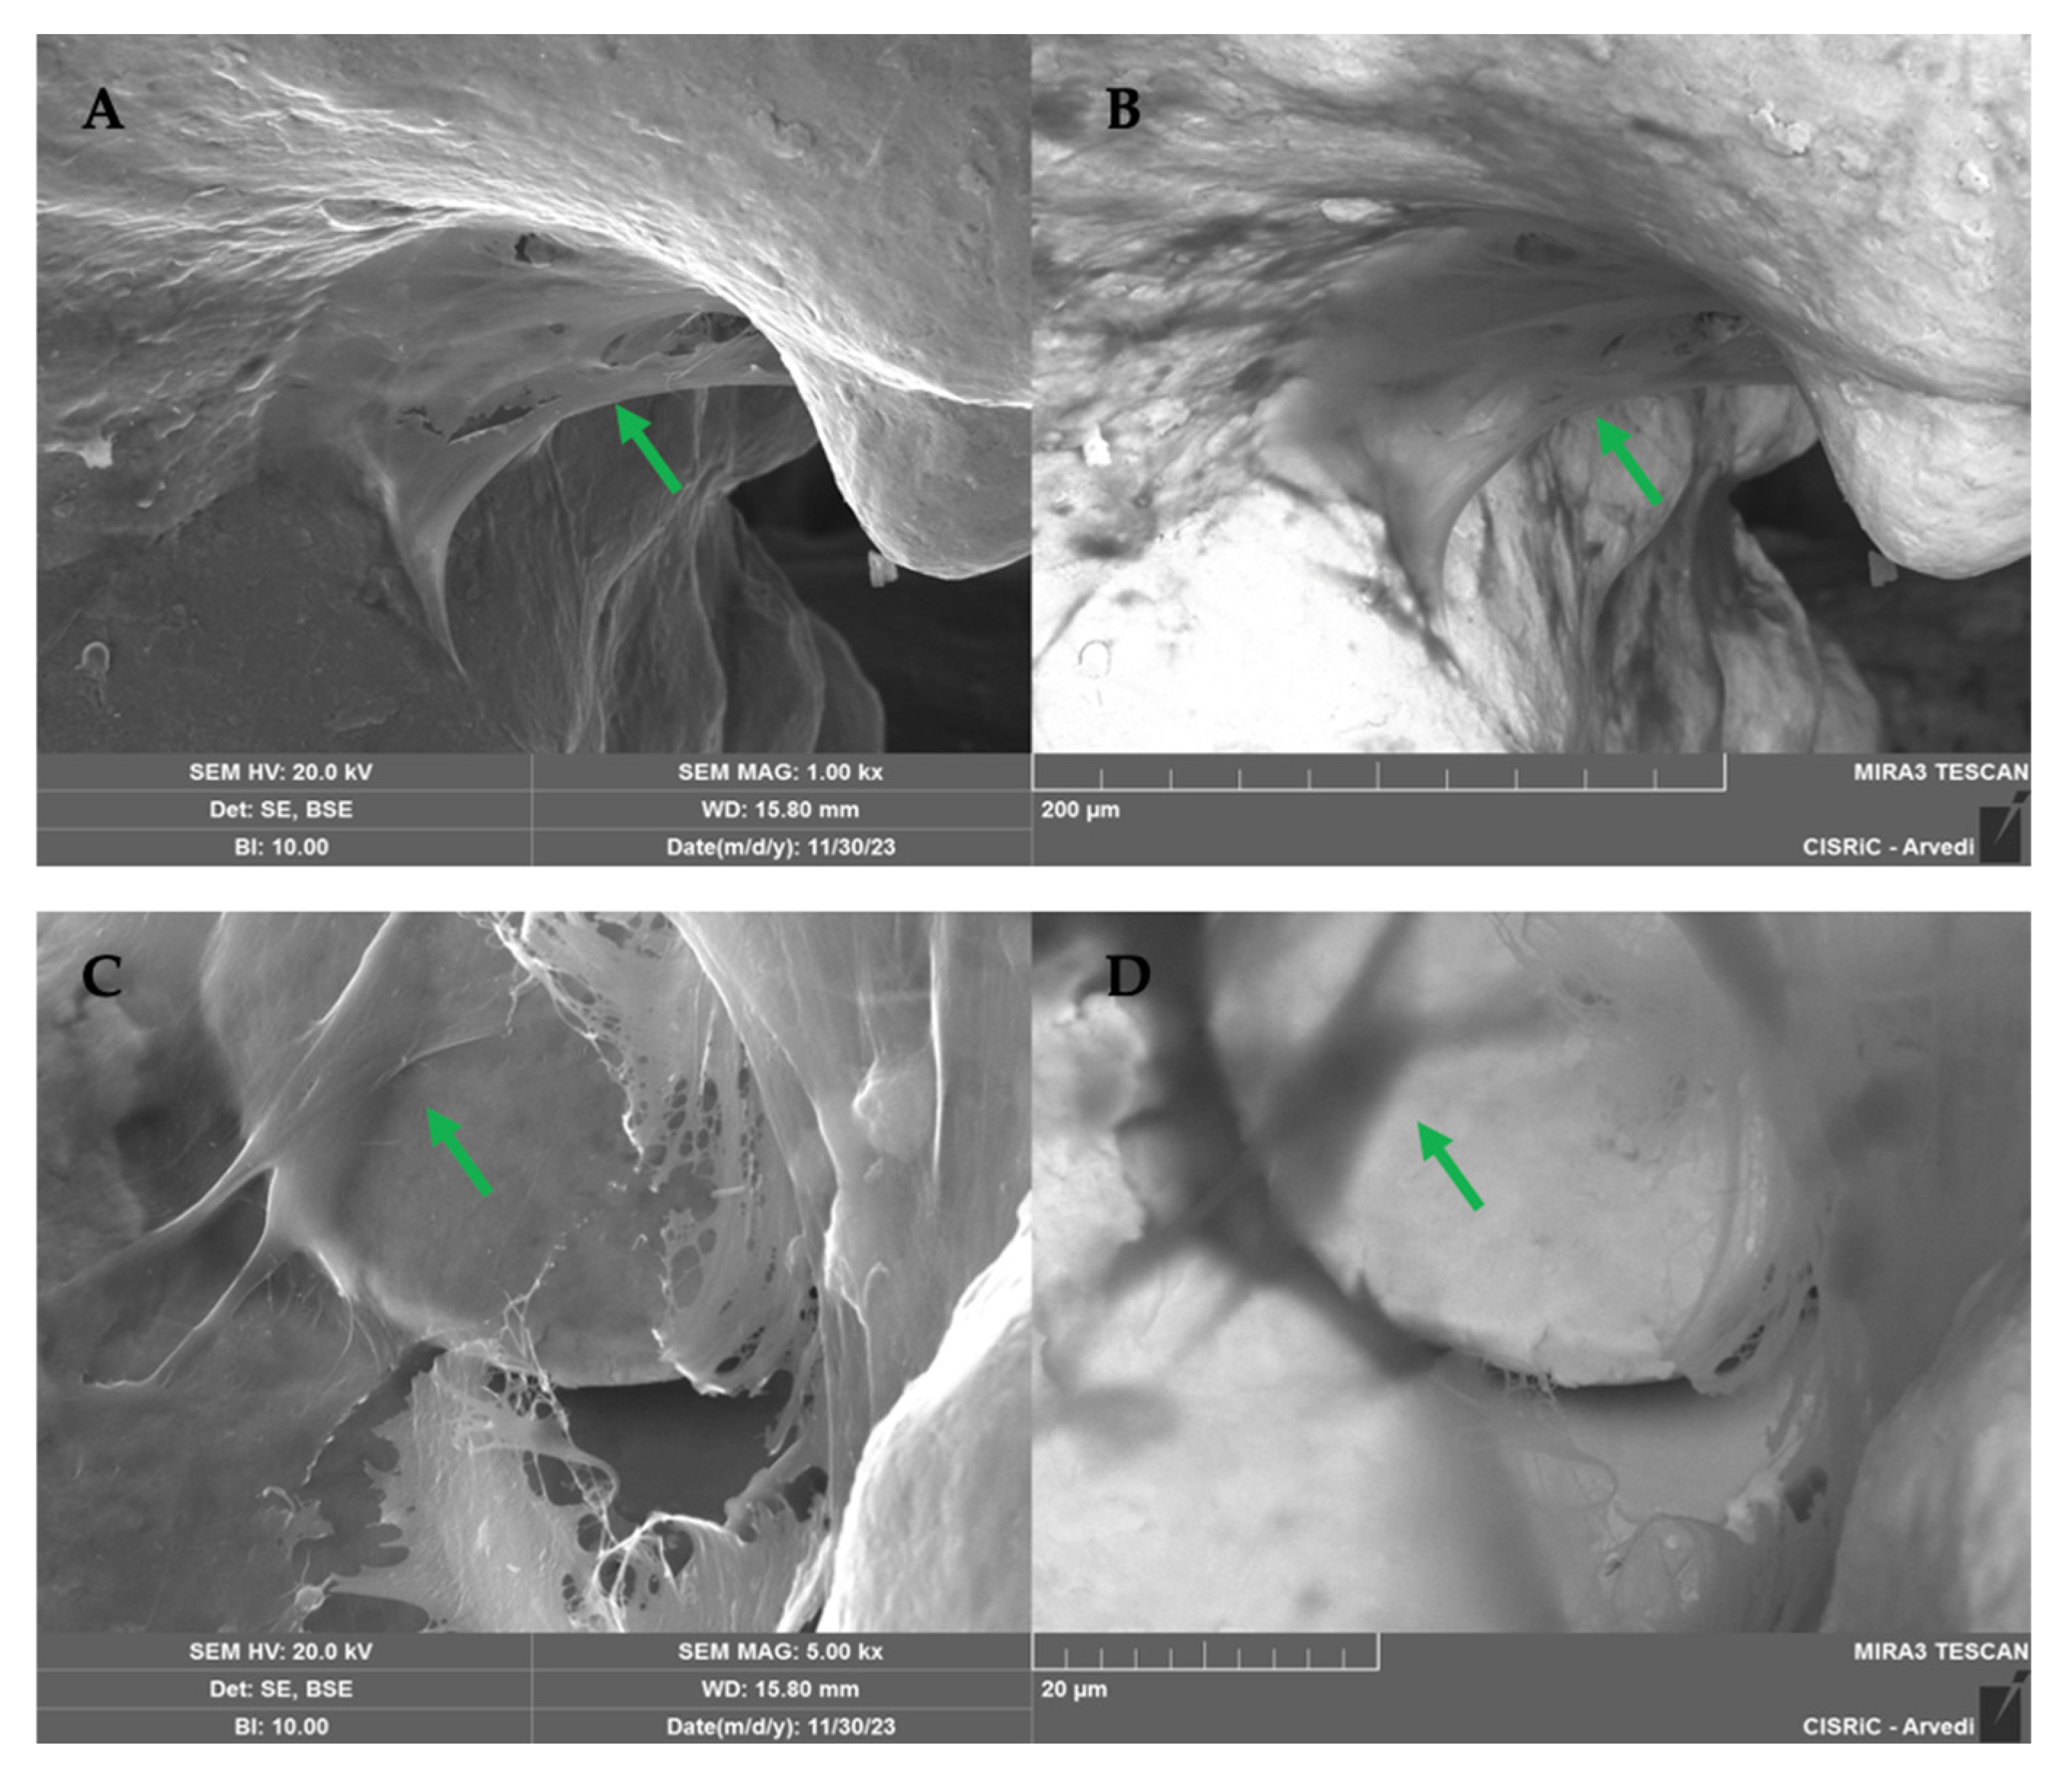

2.1.5. SEM Analysis

3. Discussion

4.10. Scanning Electron Microscope (SEM) Analysis